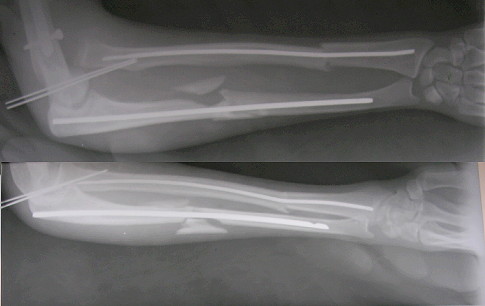

Dear All, Another case being put up on behalf of my colleague20 yrs old active male. RTA 7 weeks ago. Closed # both bones forearm with anterior dislocation of the radial head, closed # midshaft humerus same side, crush injury left lower limb beyond salvage.

At the place of first management, the radius and ulna were fixed intramedullary by closed method, some reduction of the radial head achieved and an attempt made to keep the radial head in position. BK amputation was done. Three days later, he shifted to another hospital where the humerus was fixed with a locked nail and findind the radial head remaining dispalced anteriorly an attempt was made to reduce the radial head closed.(without success). Now the patient has the radial head still displaced anteriorly. There is no radial palsy. My suggestion was as follows:The reason for the head not getting reduced is at least partially due the length of ulna not having been restored.ExFix of any type in the ulna, distract till the legth is restored and try to reduce by flexing the elbow to extreme flexion. If necessary open reduction of the radial head and retain with a sling made of fascia lata.Your comments are welcome. RegardsV M Iyer. Iyer Orthopaedic Centre, 103,Railway lines Solapur India

Not likely to my view. The problem goes from 1)the annular ligament rupture and 2)the wires missed the radial head - they are not even bent while the head is out of its position after the "fixation".

There is a well established Ilizarov technique for forearm fractures and particularly the Monteggia conponent - after closed reduction the proximal radius is fixed by an olive wire, it is a single wire through the both bones.

Кликните для загрузки файла forearm.gif